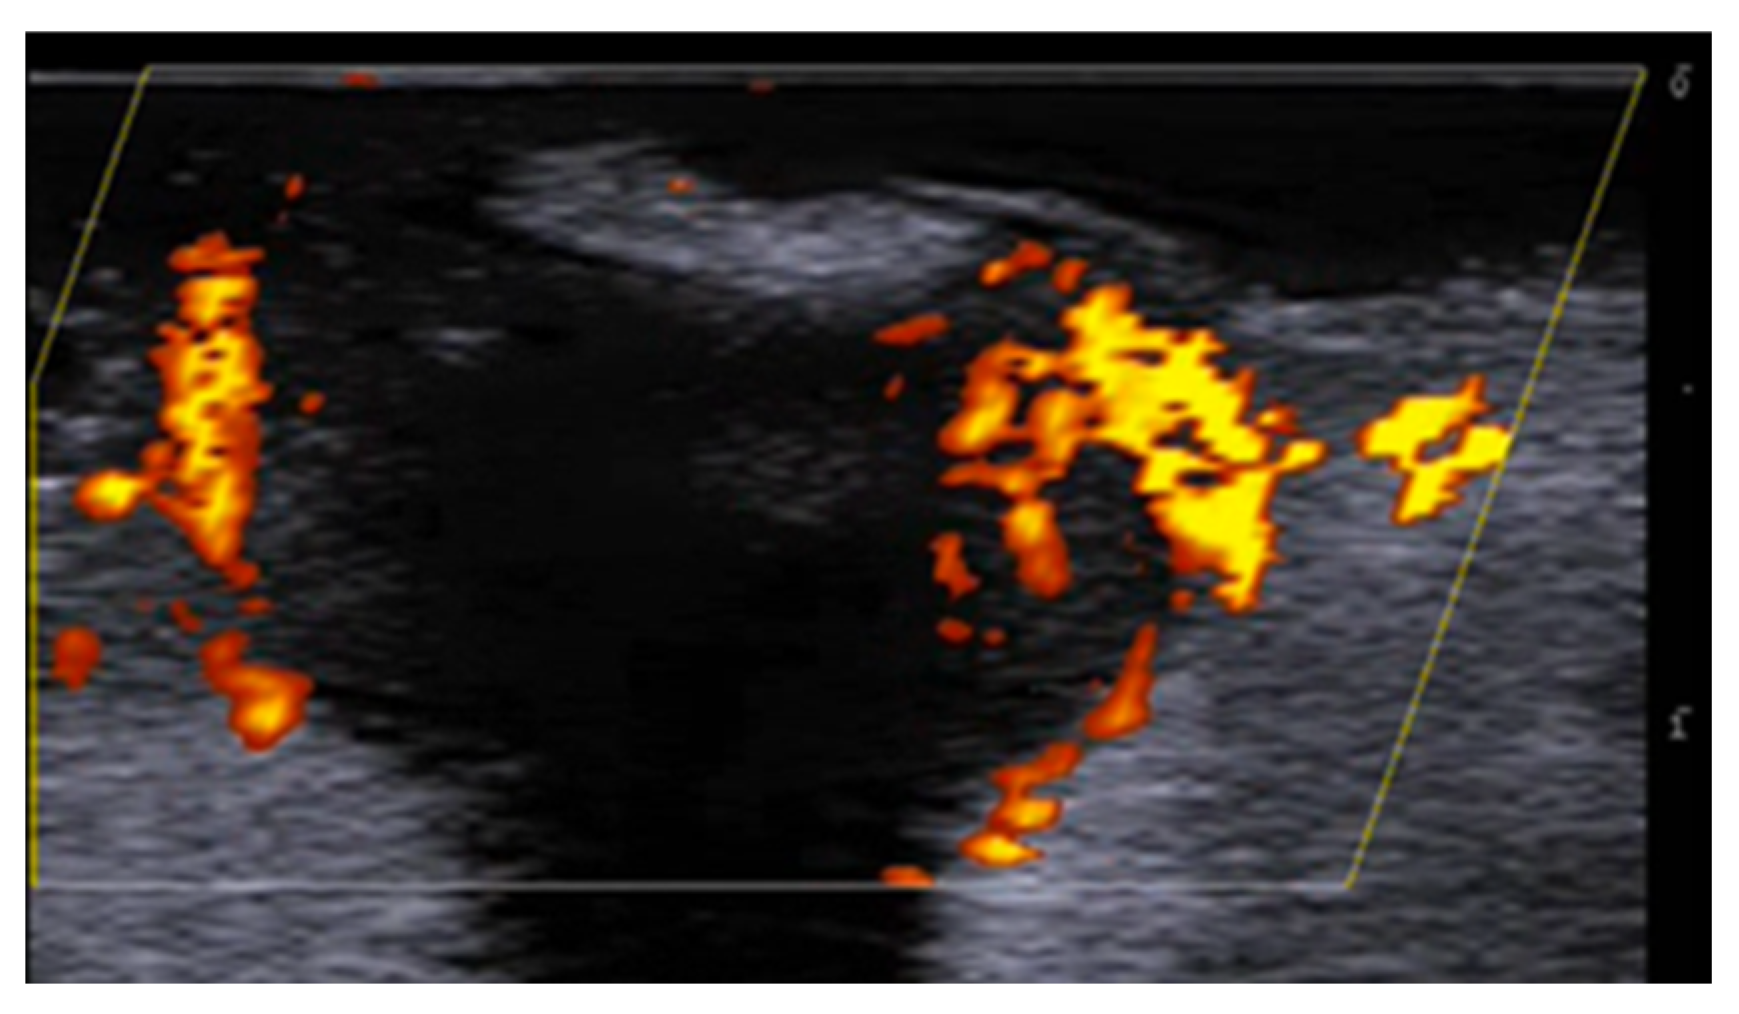

- Di Battista, M.; Vitali, S.; Barsotti, S.; Granieri, G.; Aringhieri, G.; Morganti, R.; Dini, V.; Della Rossa, A.; Romanelli, M.; Neri, E.; et al. Ultra-high frequency ultrasound for digital arteries: Improving the characterization of vasculopathy in systemic sclerosis. Semin. Arthritis Rheum. 2022, 57, 152105. [Google Scholar] [CrossRef] [PubMed]